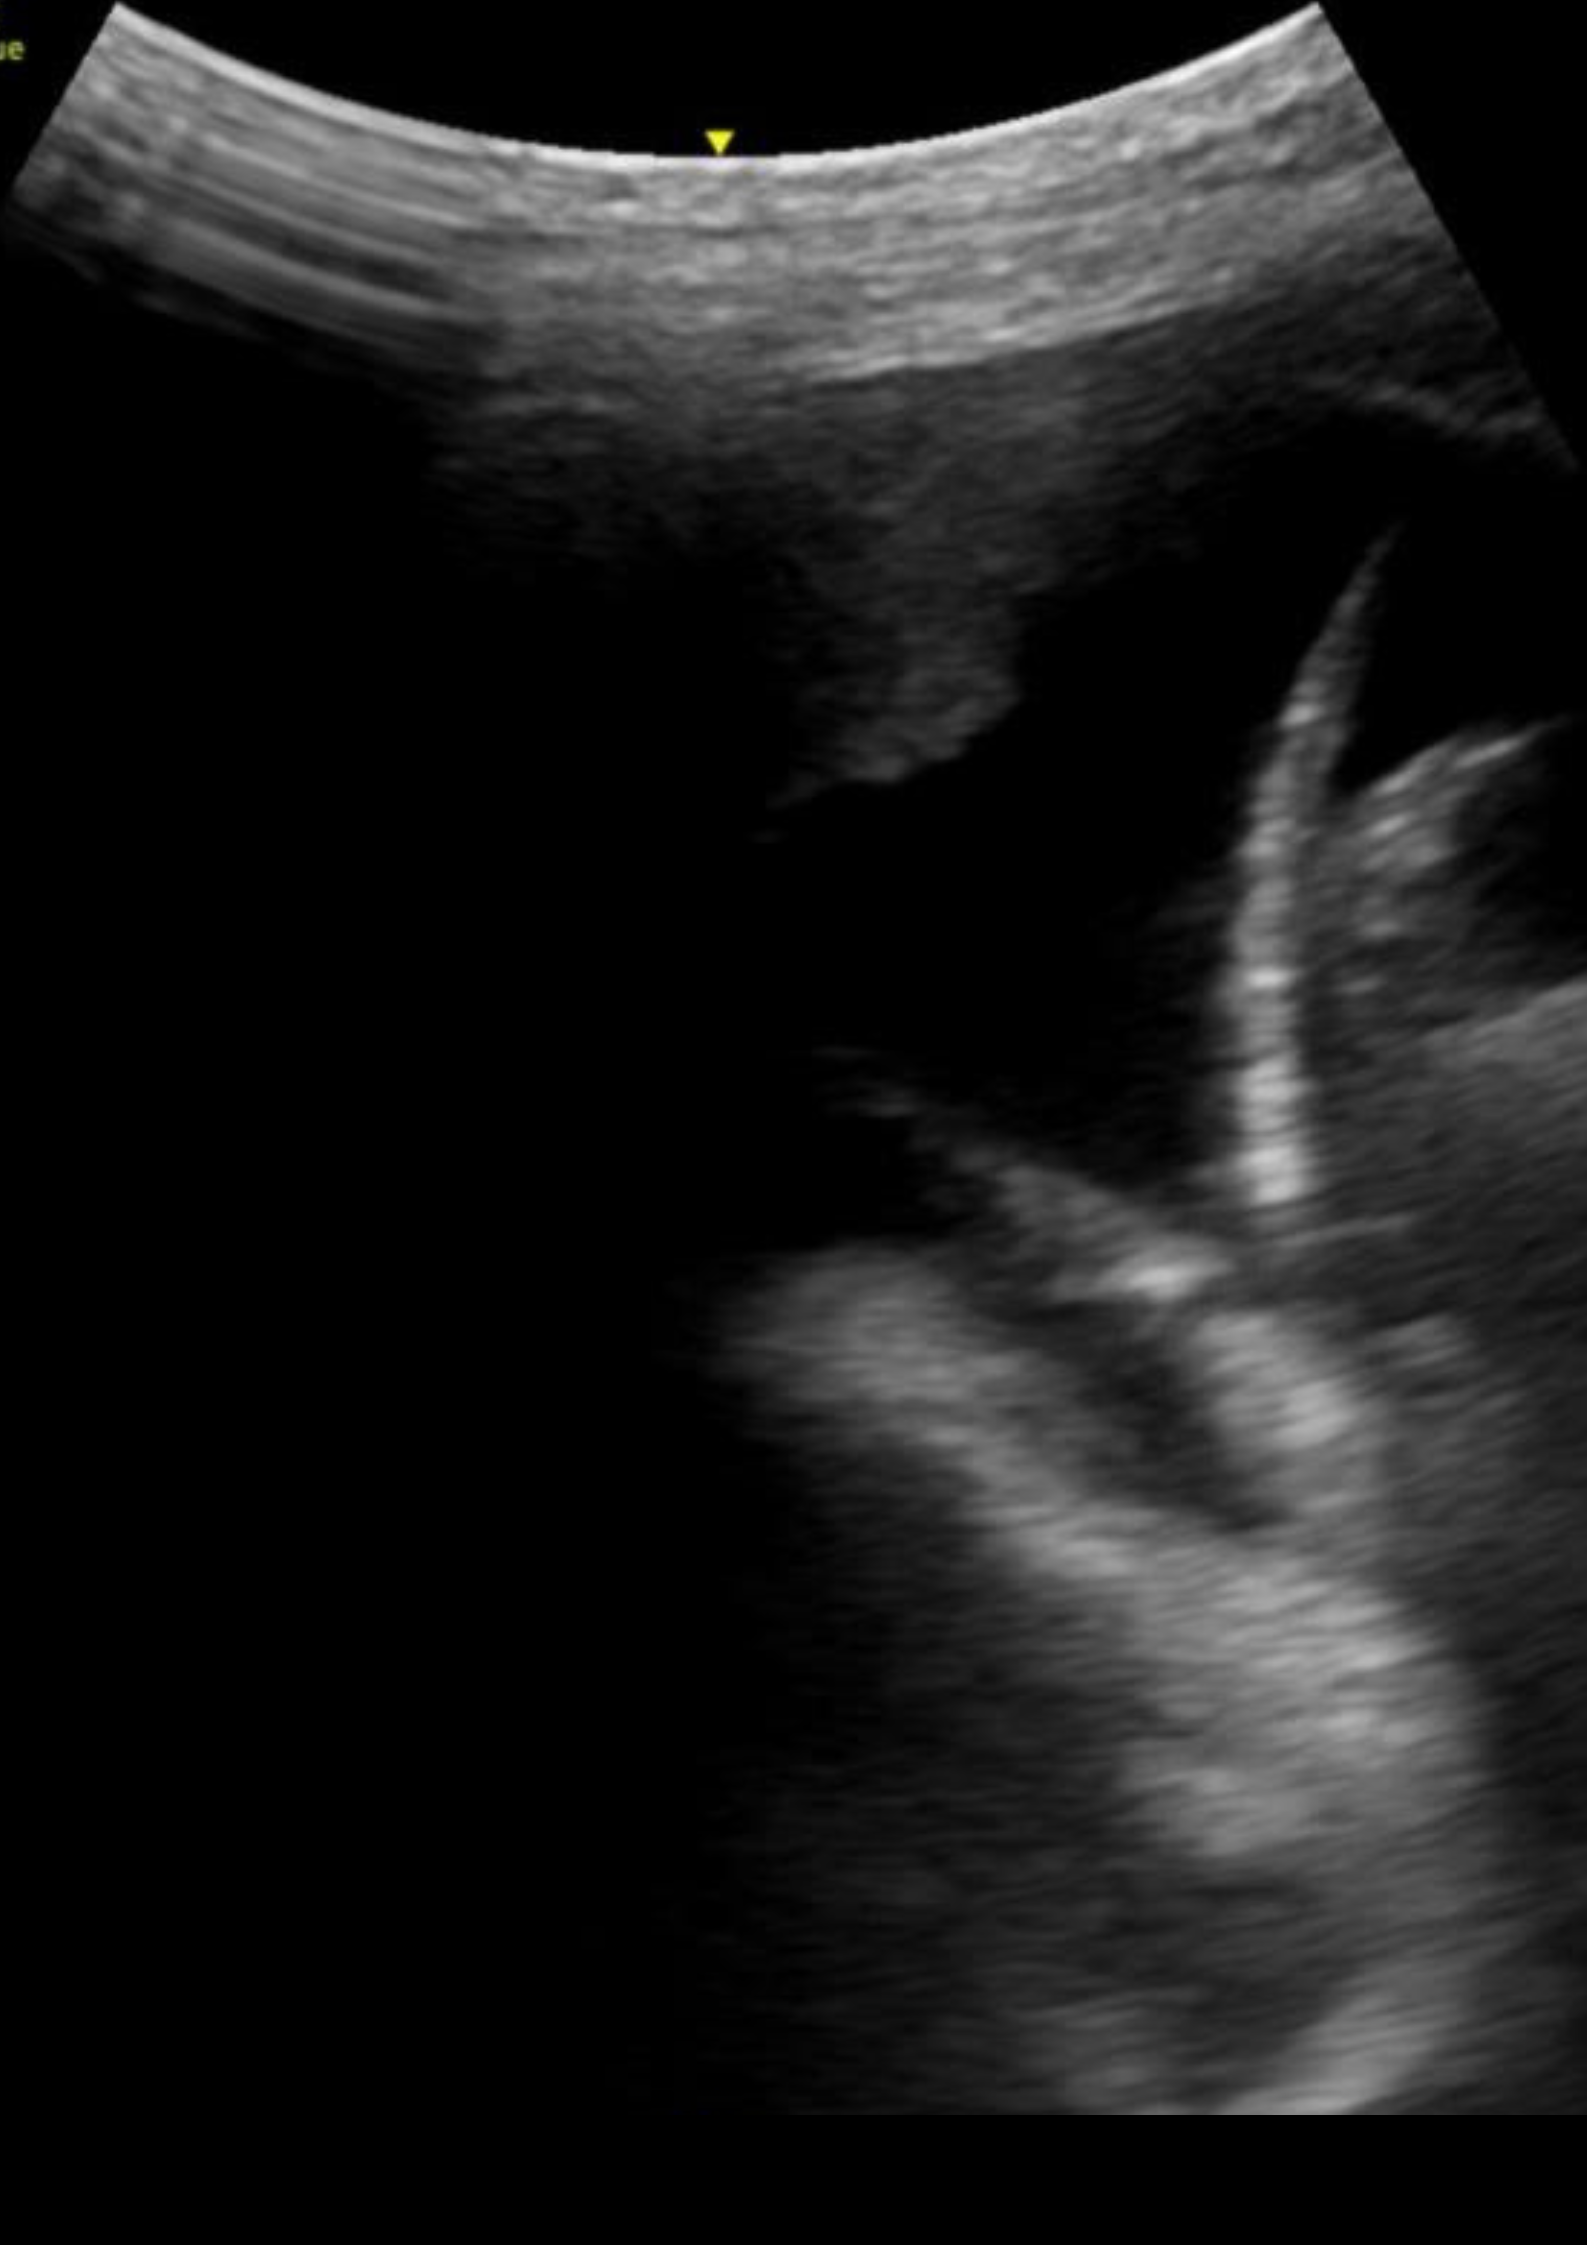

En la ecografía pulmonar observamos varios patrones de líneas B bilaterales de predominio derecho, con hallazgo de consolidación en punto PLAPS (posterolateral alveolar and/or pleural syndrome) y derrame pleural.

La ecografía pulmonar en Atención Primaria no está tan establecida como en el caso de Urgencias, sin embargo, un correcto manejo de la misma permite diferenciar entre diferentes motivos de disnea como son la descompensación cardíaca y el broncoespasmo, así como patología infecciosa. El punto PLAPS, situado en la parte postero-inferior-lateral del pulmón, es el punto más rentable para el diagnostico de las consolidaciones pulmonares así como el derrame pleural, independientemente de la posición del paciente.